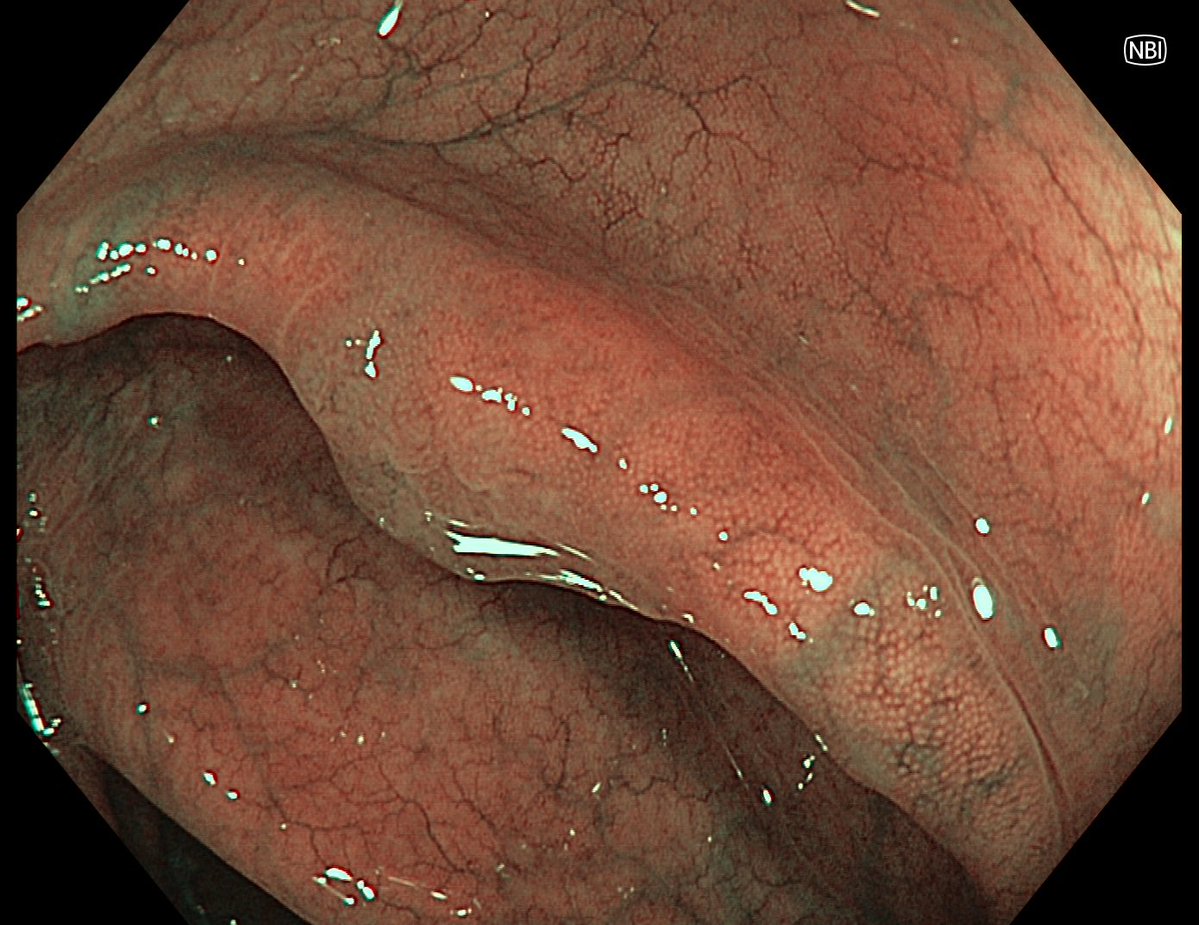

This lesion was diagnosed in the distal sigmoid colon? What do you do next?